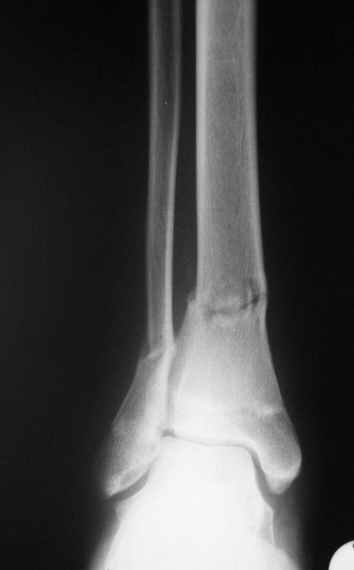

Отправитель: Evgueny Tchekashkine 01 Апрель 2005, 22:45

Как ты тут оцениваешь восстановление оси большеберцовой кости?

Согласный я с тобой:-)) есть остаточная вальгусная деформация (по снимку видно перекрывание дист. фрагментом б.б по латеральной поверхности проксимальноо фагмента на 2-3 мм и наружная лодыжка репонирована с укорочением, судя по прямой проекции. Необходимость использования интраоперационно дистрактора была бы оправдана (вручную было непросто *вытянуть* дистальный отломок.)

На мой взгляд, Ваша демонстрация неожиданно добавила перцу. Если память мне не изменяет, я говорил об отсутствии показаний к остеосинтезу малоберцовой.

Сейчас можно заикнуться о вредности этой манипуляции с точки зрения риска фиксации в неправильном положении, как это получилось у Вашего пациента. Сначала фиксировали большеберцовую, и надо было на этом остановиться, ин май хамбл опиньон. Потом при закручивании винтов на мощнейшей второй пластине сустав увело на вальгус. С учетом того, что пацану всего 17, я бы удалил пластину с малоберцовой и попытался тем или иным способом устранить смещение, пока не срослось.